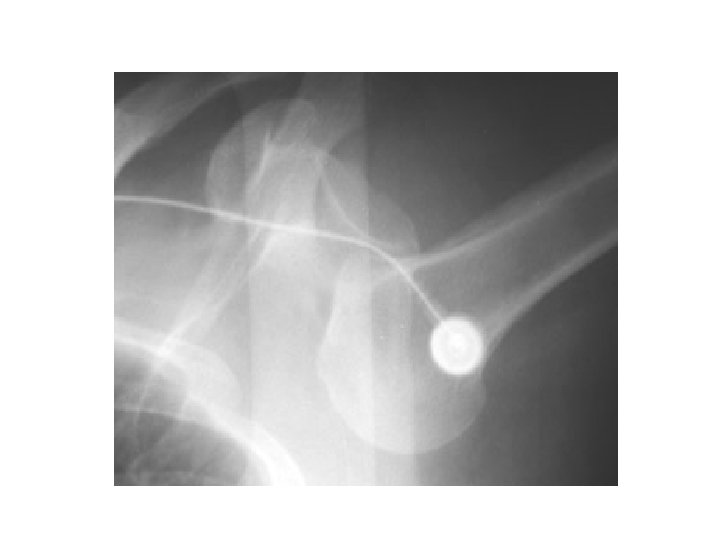

Bankhart

Complications of anterior glenohumeral dislocation and reduction • Neurovascular – neuropraxic and recover in days-weeks • Fractures – Hill-Sachs – 11 -50% of ant dislocations. May be higher if consider minor compression fractures – Bankart – ant glenoid rim #. 5% of cases. – Avulsion # of greater tuberosity in 10 -15%.